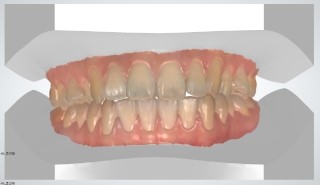

3D 시뮬레이션을 통한 교정결과 예측